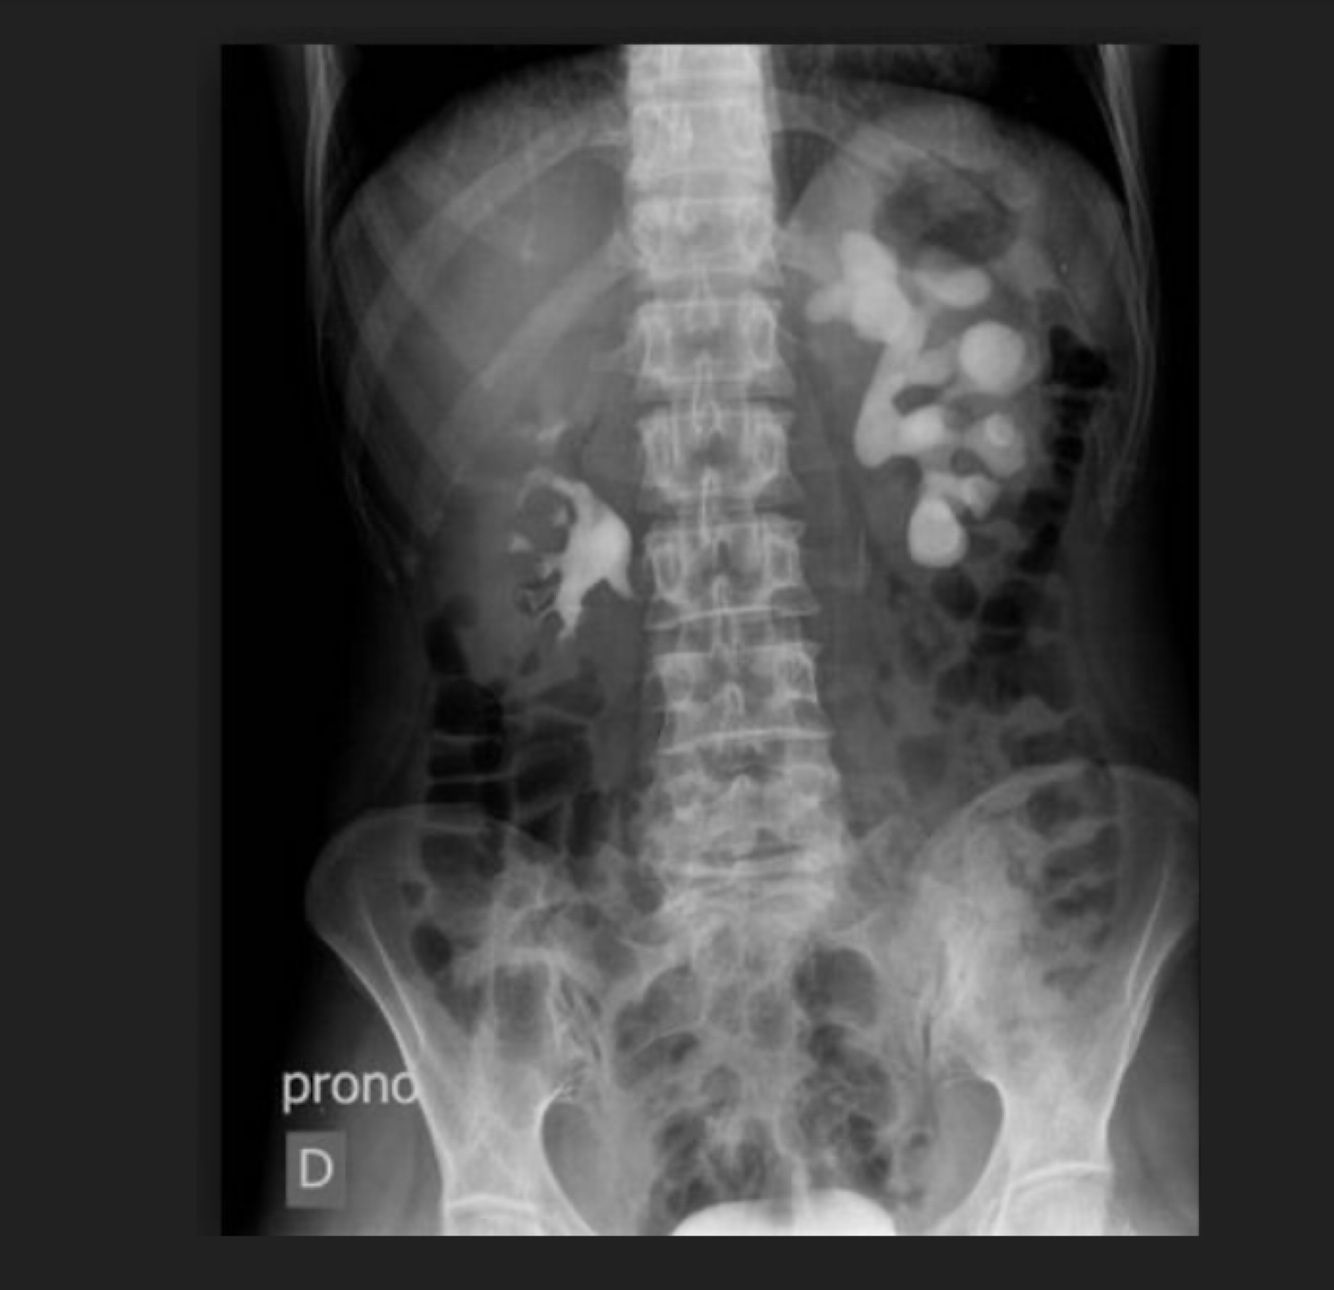

Q

La Imágen nos muestra:

A

Ectopia renal